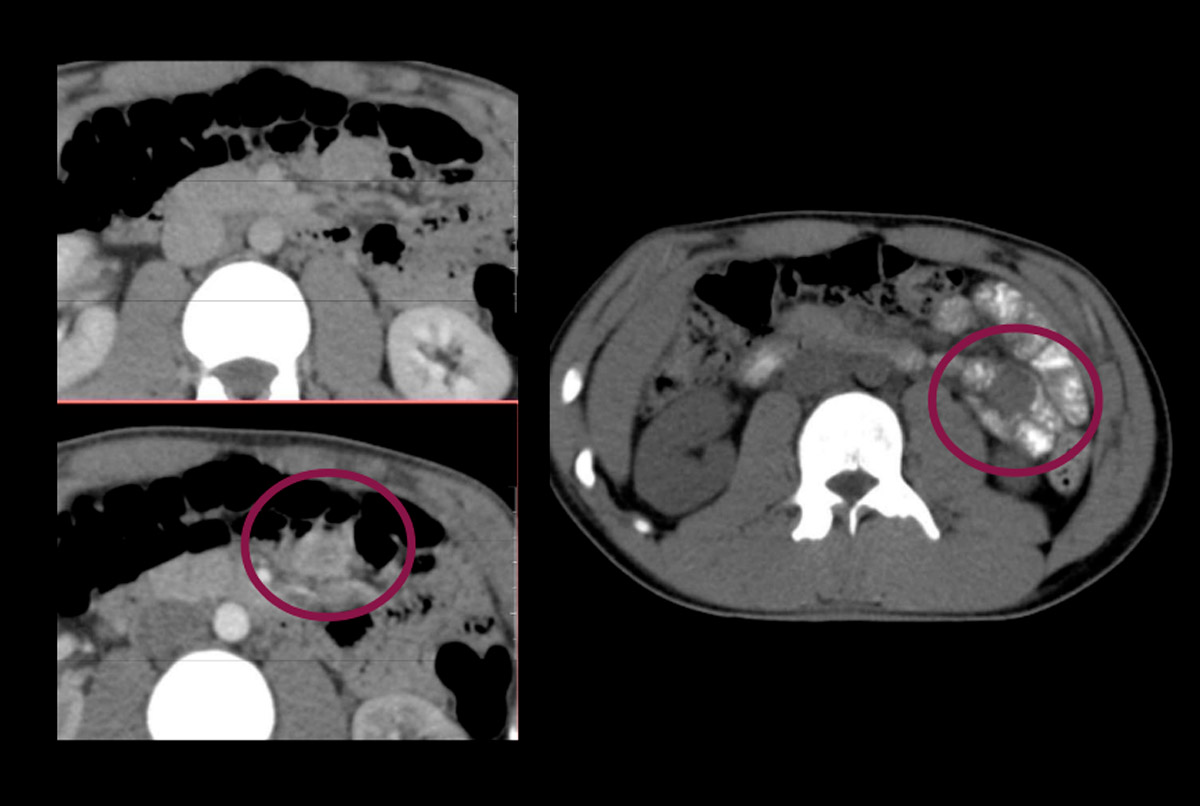

Masculino – 18 años

· Consumo de AINES por cervicalgia crónica

Antecedente de internación reciente por HDA + anemia con requerimiento transfusional en otro nosocomio en contexto de gastritis eritematosa.